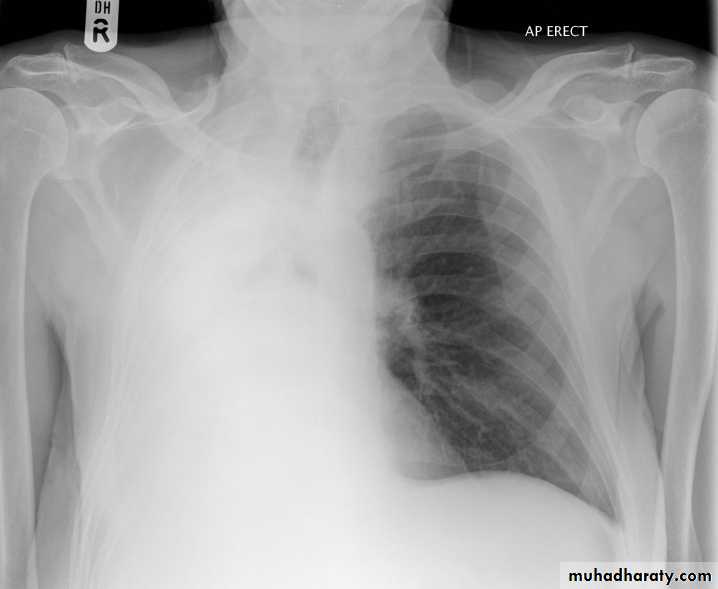

Pleural effusion

50.pleural effusion

51.pleural effusion .